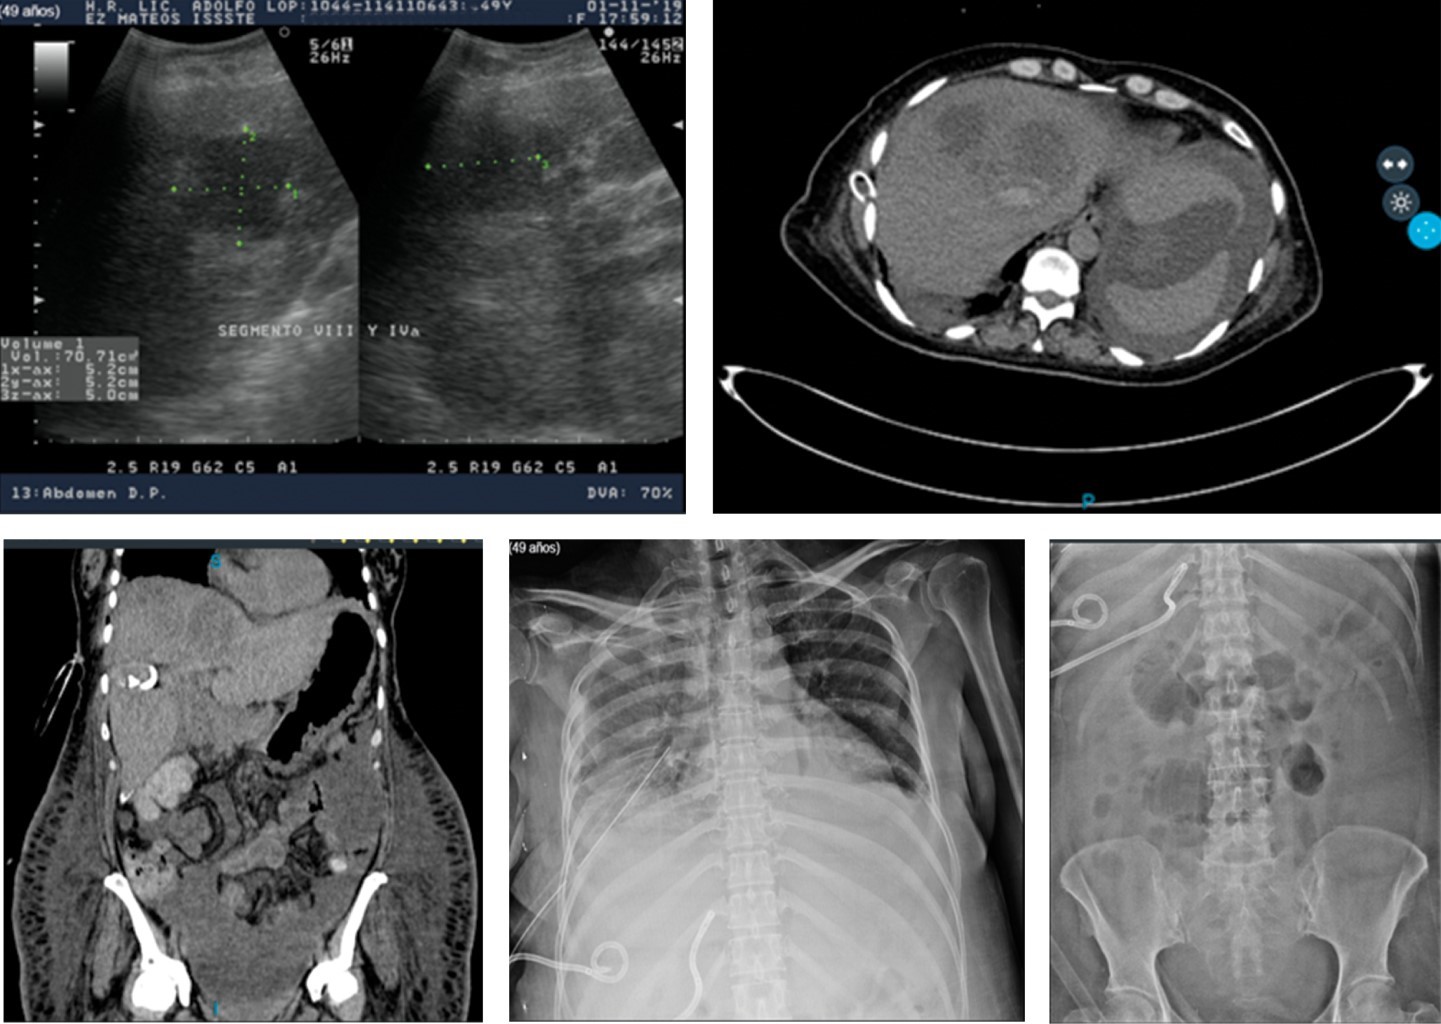

Se realiza a su ingreso USG de hígado y vías biliares reportando glándula hepática de parénquima heterogéneo con imagen hipoecoica, de bordes poco definidos, diámetros de 6.37 × 5.23 cm localizada en el segmento VI, heterogénea, con escasa vascularidad sugestiva de absceso hepático vs hepatocarcinoma, vasos portales conservados, conductos intrahepáticos con aire en su interior sugestivo de neumobilia, colédoco y vena porta de calibre normal. Laboratorio de un día después del ingreso con glucosa de 86 mg/dl, urea 17 mg/dl, Bun 7.9 mg/dl, Ca 6.9 mg/dl, GGT 349 U/l, BD 3.34 mg/dl, BI 1.29 mg/dl, BT 4.63 mg/dl, FA 410 U/l, AST 37 U/l, ALT 28 U/l, DHL 131 U/l, Na 134 mmol/l, K 3.7 mmol/l, CL 108 mmol/l, leucocitos 13.3 x 103/μl, neutrófilos 85.1%, HB 10.4 g/dl, HTO 30.2%, PLT 220 x 103/μl, TP 15.6 seg, TPT 34.7 seg, INR 1.16.

Se le realiza TC abdominal el 02-10-19 que reporta hallazgos de imagen hipodensa de 80 × 53 mm con 23 UH en el segmento VI y VII, en relación con absceso hepático del lado derecho, hepatomegalia a expensas del mismo lóbulo, presencia de neumobilia, la cual aparentemente se observa en comunicación con la pared anterior de la vesícula biliar, escaso líquido libre en hueco pélvico, derrame pleural bilateral y atelectasias pasivas. De igual forma se solicita CPRE el 09-10-19 que reporta colédoco de 6-7 mm, conducto biliar común de 10 mm, se observa defecto de llenado circular de aproximadamente 20 mm que retrasa el vaciamiento del medio de contraste de la vía biliar reportando probable síndrome de Mirizzi tipo IV y fístula bilioentérica de sitio a determinar. Se realiza esfinterotomía, barrido con cánula litotriptora y colocación de endoprótesis tipo Ámsterdam de 10 × 10 cm (Figura 2).

En terapia intensiva se realiza nuevo USG abdominal (1-XI-19) y se moviliza después al Servicio de Radiología para realizar TC simple y contrastada de abdomen, efectuándose una primera punción ese mismo día y ante la falta de drenaje y no disminución de la colección se realiza una segunda punción el 7 de noviembre de 2019 dejándose dos colas de cochino con catéteres de 8 Fr en dos de las colecciones mayores (Figura 6).

Se reinició la vía oral con dieta líquida y papillas retirándose paulatinamente la nutrición parenteral total y habiendo cedido la fiebre, mejorado su redistribución de líquidos corporales y los gastos de los drenajes hepáticos disminuido a menos de 40 cm3 en 24 horas, la paciente fue egresada a su domicilio el 20-11-2019 con cefalexina 500 mg c/6 horas, vía oral durante 15 días más y vigilancia de las pequeñas colecciones hepáticas remanentes con USG mensual durante tres meses en la consulta externa (Figura 7).